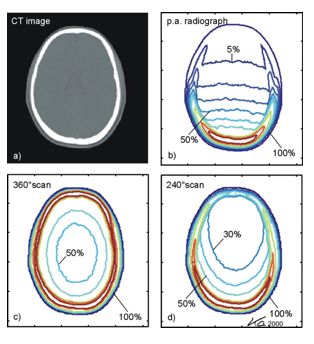

单次扫描剂量可采用剂量指数(CTDI)来描述:

CTDI是长度剂量乘积除以断层厚度的商。长度剂量乘积是地区性剂量对整个剂量剖面在轴上的积分。

美国的FDA(美国食品药品监督管理局)对剂量指数(CTDI)作如下定义:

我国的国家标准对剂量指数(CTDI)作如下定义:

沿着垂直于体层平面方向上的剂量分布除以X射线管在360 °的单次旋转时产生的体层切片的数目N与标称切片厚度T的乘积从-50mm到+50mm的积分。